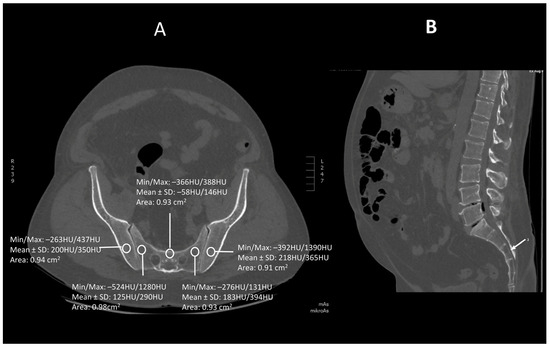

Figure 3.

A transverse (A) and saggital (B) projection of CT scan in level S3. A circular region of interest (ROI) ranging from 0.8 to 1.2 cm2 has been placed at the ala of the ilium, the wing of the sacrum and the body of sacral vertebra 3.

Images were viewed using the bone algorithm default windows. The investigator first determined axial images in levels of mid-lengths of bodies of sacral vertebrae 1, 2 and 3 that afterward were confirmed by coronal and sagittal reconstructions (Figure 1, Figure 2 and Figure 3). The volumetric bone density expressed in HU values was measured in sacral levels of S1, S2 and S3. Apart from the bodies of sacral vertebrae S1–S3, the measurements involved the ala of the ilium in the vicinity of the sacroiliac joint and the wing of the sacrum. All the measurements were performed on the pathway of presumptive iliosacral screws to stabilize the sacroiliac joint.

In order to standardize measurements while accounting for normal anatomic variations and optimum iliosacral screw trajectories—so as to avoid injuries of neurovascular structures—standardized circular voxel regions of interest (ROIs) were drawn (Figure 1, Figure 2 and Figure 3) [12]. As presented in the former studies, these ROIs were drawn in levels of mid-lengths of the bodies of sacral vertebrae 1, 2 and 3, the right and left wings of sacrum and the ala of the ilium in sacral levels of S1–S3 [13]. The aforementioned standardized ROIs were drawn with areas ranging from 0.8 to 1.2 cm2. This range of area was estimated as it best represented the osseous surface area, which is required to safely place 7.0–mm iliosacral or transsacral screws [4].